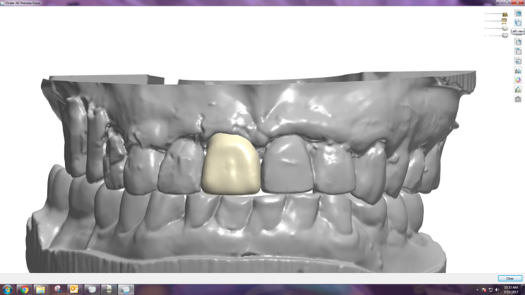

Fig 10. Titanium abutment proposal.

Figure 10

Fig 11. Final crown proposal.

Figure 11

After 4 months of healing and integration of the bone around the implant, the digital workflow was initiated to develop the abutment and treatment plan. Another analog impression was made with an impression post and polyvinyl impression. The laboratory scanned the impression and digitized it to create the emergence profile of the milled titanium abutment and the final restoration (Figure 10 and Figure 11). The patient had a considerably thick soft-tissue profile, allowing a milled titanium abutment. The decision to use a titanium abutment was based on the patient's occlusion and propensity to fracture teeth or restorations. The virtual model was gray because the scanner does not recognize the color of the analog impression. The virtual final abutment and crown were approved and fabrication completed. The final restoration met the patient's esthetic values and his ability to function (Figure 12 and Figure 13).